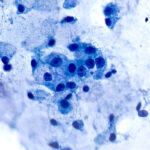

Slide Quality

Our propriety monolayer preparation ensures minimal cellular overlap, giving a clear view of cellular features. Every slide looks expertly done—even without the expertise.